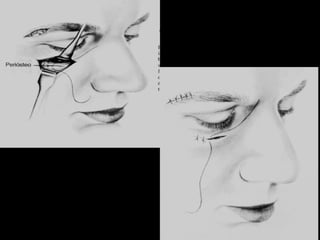

TRATAMENTO DA FRATURA DO ZIGOMA CIRÚRGICO ANESTESIA GERAL ABORDAGENS:  EXTRA-BUCAL INTRA-BUCAL SUPRACILIAR PALPEBRAL INFERIOR MÉTODO DE GILLIES TRANSCUTÂNEA

TRATAMENTO DAS FRATURAS DO COMPLEXO MAXILOZIGOMÁTICO   fraturas da arcada zigomática Abordagem temporal ou Método de Gillies 1. Preparo do local da incisão: raspar o cabelo da região temporal; 2. Incisão  (2cm) da pele e da aponeurose temporal,  3. Desliza-se um instrumento (forte elevador ou espátula de Rowe-Bristow), na fossa temporal, sob a arcada zigomática;

TRATAMENTO DAS FRATURAS DO COMPLEXO MAXILOZIGOMÁTICO   fraturas da arcada zigomática Abordagem temporal ou Método de Gillies 4. Uma forte ação de alavanca é exercida tendo como fulcro um maço de gaze colocada na reg. parietal e reduz a fratura, enquanto a outra mão palpa as estruturas através da pele; 5. Há um engrenamento dos fragmentos ósseos, o que mantém a estabilidade da fratura.

ABORDAGEM TRANSCUTÂNEA